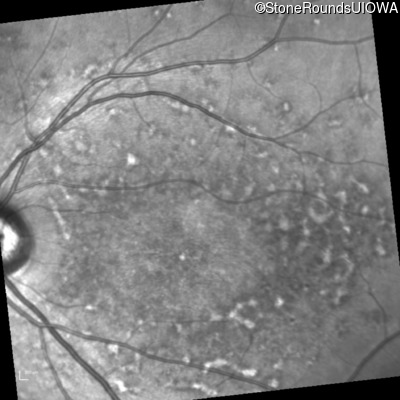

AR Stargardt Disease (IIA)

This 22 year old woman first had difficulty seeing the blackboard at age 14 and this was not correctable with glasses.

Age at visit: 17 years

Age at visit: 18 years

Age at visit: 19 years

Age at visit: 22 years